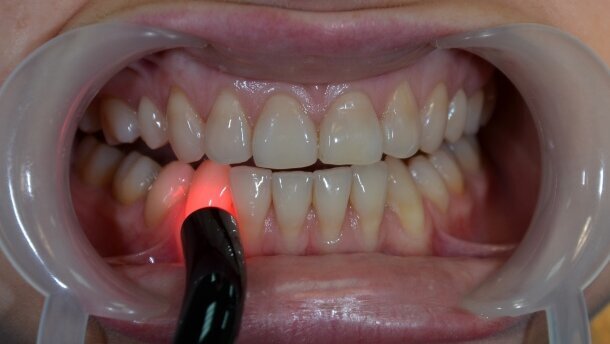

W badaniu wykorzystano laser diodowy SmartM®, używając sondy zabiegowej z aplikatorem światłowodowym, kątowym o średnicy 0,8 cm. Parametry zabiegu: długość fali 635 nm, moc 40 mW, dawka energii 5J/cm², praca ciągła. Każdy ząb naświetlano metodą bezkontaktową w 2 miejscach po 60 s: w okolicy szyjki (Ryc. 3) oraz w rzucie wierzchołka korzenia (Ryc. 4).